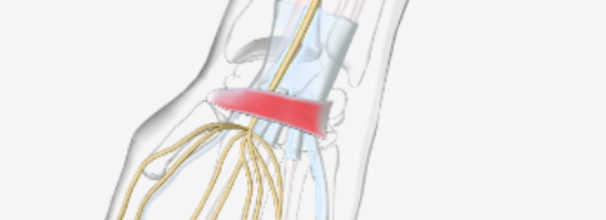

- טניס אלבו – תרגילים לטניס אלבו, דלקת במרפק, כאבים במרפק